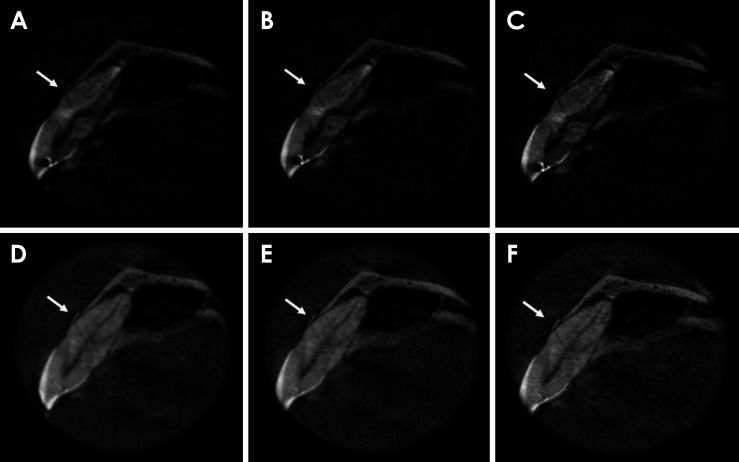

目的:本研究探讨了减少金属伪影(MAR)、应用锐化滤波器及其组合对锥形束计算机断层扫描(CBCT)检查中氧化锆种植体邻近牙齿水平根折(HRF)诊断的影响:将 19 颗单根牙齿(9 颗有 HRF,10 颗没有 HRF)分别置于干燥人类上颌骨的右中切牙牙槽窝中。每颗牙齿旁边都植入了一颗氧化锆种植体。成像使用 OP300 Maxio CBCT(Instrumentarium,芬兰图苏拉)设备进行,设置如下:8 mA 电流、两种 MAR 模式(启用和禁用)、5×5 cm 视场、0.085 mm 像素大小和 90 kVp 峰值电压。四名口腔颌面部放射科医生在两种 MAR 条件下和 3 种锐化滤镜应用水平(无、锐化 1× 和锐化 2×)下独立评估 CBCT 扫描。诊断指标通过双向方差分析(α=5%)进行计算和比较。加权卡帕检验用于评估 HRF 诊断中检查者内部和检查者之间的可靠性:结果:MAR工具的激活、锐化滤波器的使用及其组合对HRF诊断的接收者工作特征曲线下面积、灵敏度或特异性没有显著影响(P>0.05)。检查者内部和检查者之间的一致性从一般到相当可观不等:结论:氧化锆种植体邻近牙齿的 HRF 诊断不受 MAR 激活、锐化过滤器应用或这些工具组合的影响。

Materials and methods: Nineteen single-rooted teeth (9 with HRF and 10 without) were individually positioned in the right central incisor socket of a dry human maxilla. A zirconia implant was placed adjacent to each tooth. Imaging was performed using an OP300 Maxio CBCT (Instrumentarium, Tuusula, Finland) unit with the following settings: a current of 8 mA, both MAR modes (enabled and disabled), a 5×5 cm field of view, a voxel size of 0.085 mm, and a peak kilovoltage of 90 kVp. Four oral and maxillofacial radiologists independently evaluated the CBCT scans under both MAR conditions and across 3 levels of sharpening filter application (none, Sharpen 1×, and Sharpen 2×). Diagnostic metrics were calculated and compared using 2-way analysis of variance (α=5%). The weighted kappa test was used to assess intra- and inter-examiner reliability in the diagnosis of HRF.